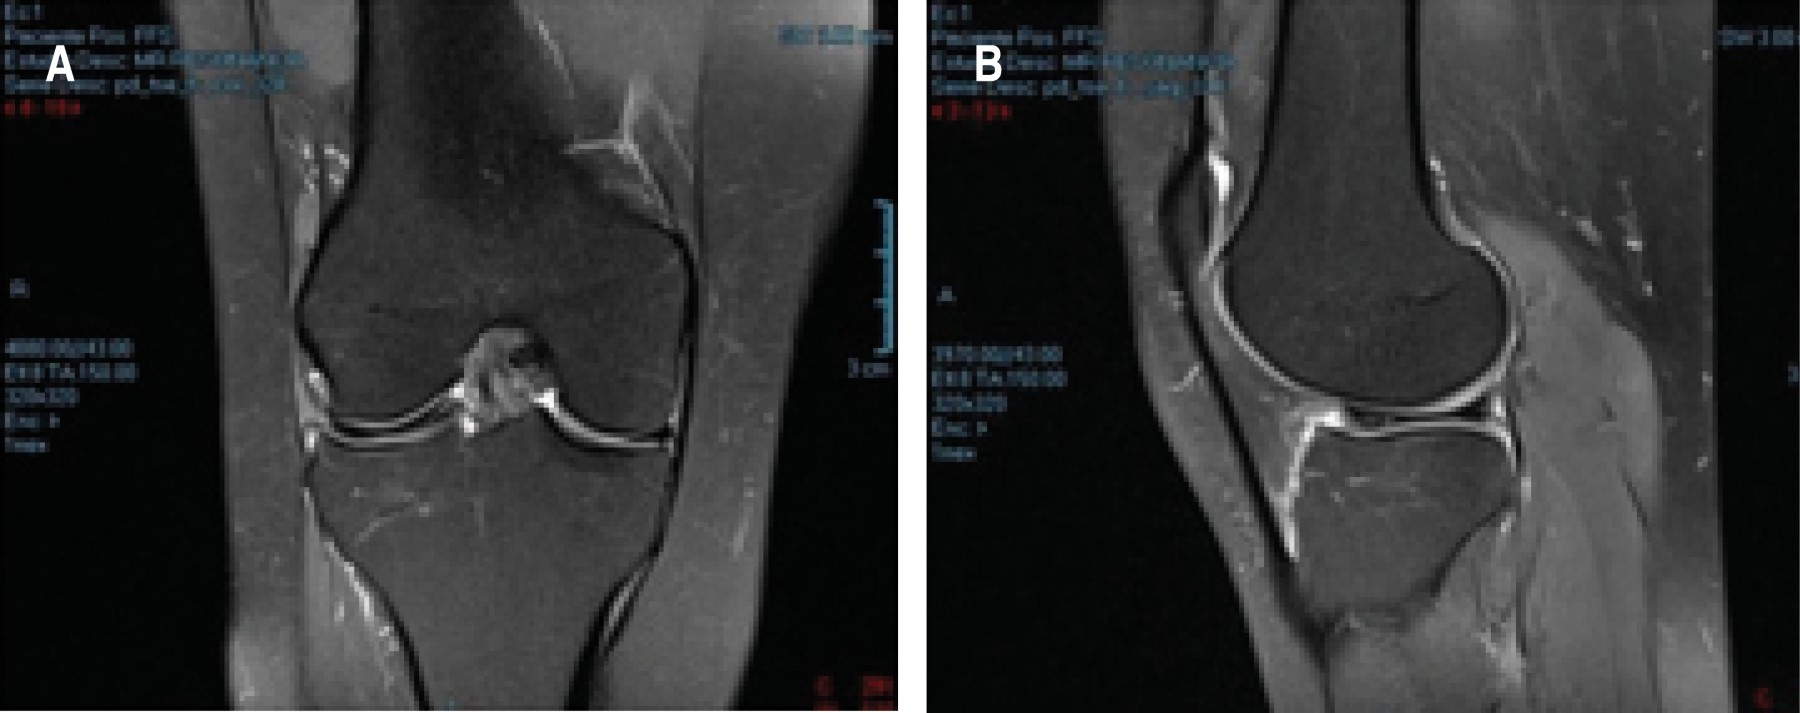

RESONANCIA MAGNéTICA

La resonancia magnética es la modalidad de elección para confirmar el diagnóstico de un menisco discoide (Figura 4).46

Determina los signos de inestabilidad periférica: ausencia de inserciones capsulares y desplazamiento anterior del cuerno posterior del menisco lateral con respecto a la tibia (subluxación del menisco).

Localiza el tipo de lesión meniscal y los desgarros intrasustanciales que no son detectables por artroscopia. Además, resulta de gran ayuda en pacientes pediátricos en quienes la exploración física es más complicada.

Silverman estableció los siguientes criterios:70

• 1. Cortes coronales: aumento del ancho del cuerpo meniscal de 15 mm o más, diferencias de tamaño entre los cuernos anterior y posterior (en condiciones normales suelen ser simétricos), menisco completo en todas los cortes de anterior a posterior (normalmente sólo está presente en las secciones anterior y posterior).

• 2. Cortes sagitales: tres o más cortes consecutivos de 5 mm de espesor que demuestren la continuidad del menisco entre los cuernos anterior y posterior (normalmente sólo se ve en dos cortes adyacentes), una apariencia anormal, engrosada y plana del menisco en su zona media y el bow-tie sign.